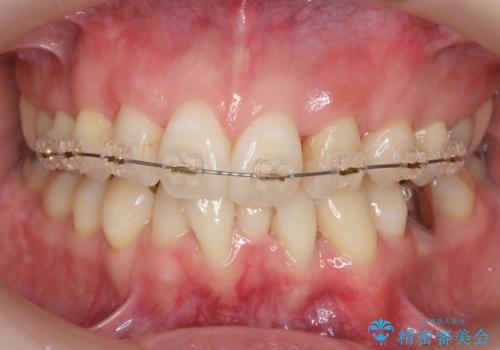

他院で3年以上かかると言われた八重歯を半年できれいに

- 八重歯を主訴に来院。他院で全体ワイヤー矯正、4本抜歯で3-4年かかるかもしれないと説明を受けたとのこと。

そこまで時間がかかるのはどうかな、でも八重歯は気になるというご相談でした。

八重歯の部分は抜歯し、奥に入っていた前歯を前に移動させました。

下の前歯は生まれつき3本だったため、さらに2本下を抜くとなると3本少なくなってしまうため、下の前歯を一本お取りして最小限の抜歯としました。

上にはワイヤー部分矯正を行った後、インビザラインでマウスピース矯正を行っています。